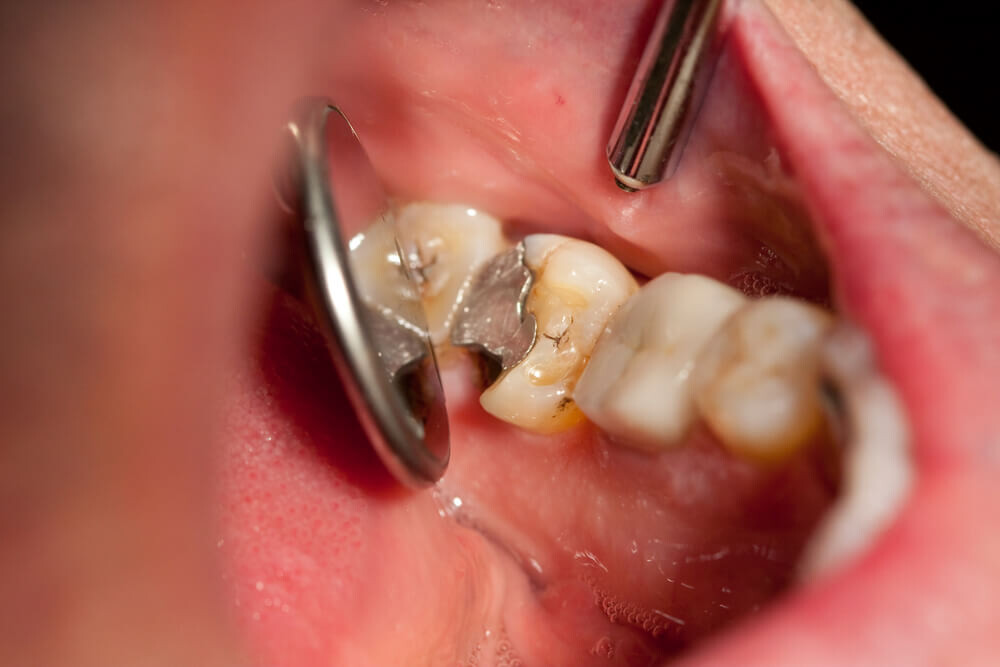

Tooth decay

As tooth decay progresses, it can reach the softer inner layers of the tooth, called dentin and pulp, resulting in sensitivity to hot, cold, or sweet foods and drinks and eventually leading to a toothache. If left untreated, tooth decay can result in an abscess, a painful infection at the root of the tooth that can cause severe pain and swelling. Adhering to your routine dental check-ups, practicing good oral hygiene, and eating a healthy diet can help prevent tooth decay and the resulting toothache.

Depending on the size of the cavity, you may be able to see evidence of it in your mouth. Cavities sometimes create visible holes in the teeth. They can also create stains that are black, brown or white on the surface of the tooth.

What should you do if you think you have a cavity? The first step is to see your dentist. Although cavities can be reversed in the early stages, by the time you are feeling discomfort or pain, only a dentist can treat them. An x-ray will be taken to determine how the cavity has progressed into the tooth. Depending on how severe the cavity is, you might need a filling to fix it. If the decay is very severe, the dentist might replace the tooth with a crown or perform a root canal.